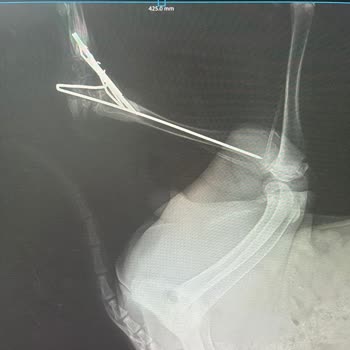

Yavru bir cana araç çarptı ve Axis Veteriner Kliniği'ne götürüldü. Ameliyat dediler, başka yolu yok, mecbur dediler. Ama maalesef hatalı, kusurlu ve yanlış bir ameliyat yaptılar. Şimdi de telefonu engellemişler. İlgisizlik ve ciddiyetsizlik var. Raporlar ve röntgenler hepsi mevcut.